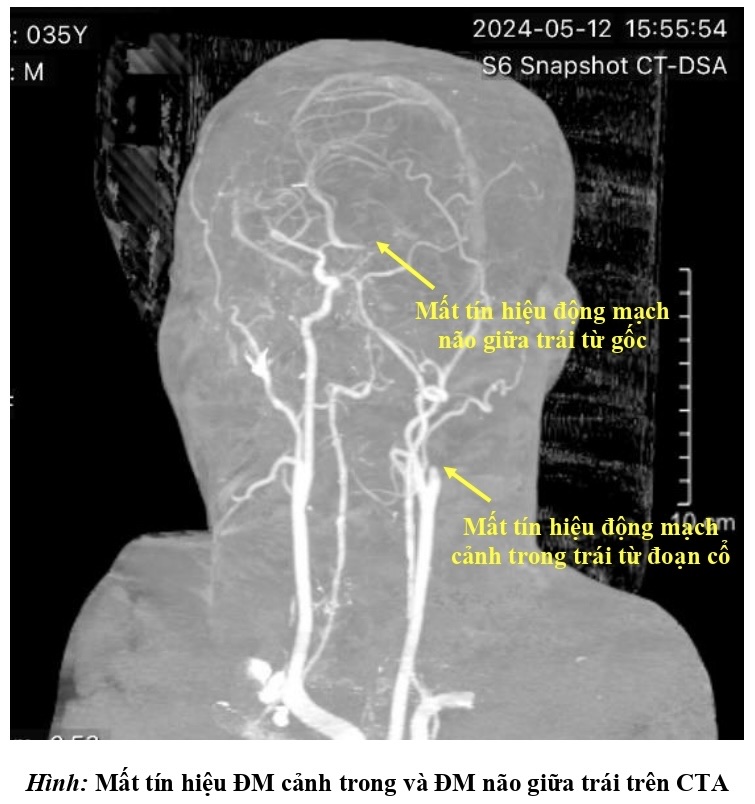

Ngay lập tức, bệnh viện kích hoạt quy trình báo động đột quỵ (code stroke). Khẩn trương thăm khám lâm sàng và cận lâm sàng, các bác sĩ chẩn đoán bệnh nhân bị đột quỵ nhồi máu não bán cầu trái giờ thứ 2 do tắc động mạch cảnh trong trái và động mạch não giữa trái bởi huyết khối.

Hình chụp CT của bệnh nhân S.

Toàn bộ bán cầu não bên trái bị ngừng cung cấp máu, đe dọa nghiêm trọng tính mạng bệnh nhân, các bác sĩ phải chạy đua với thời gian cứu chữa người bệnh.